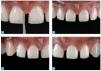

Se retira el dique de goma y se corrige la oclusión mediante un sistema de pulidores de diamante para cerámica. El tejido gingival sano estaba estable al cabo de dos semanas (figs. 35 y 36). Las figuras 37 y 38 muestran la sonrisa del paciente seis meses después del cementado.

Figs. 37 a 40. La situación final al cabo de seis meses.